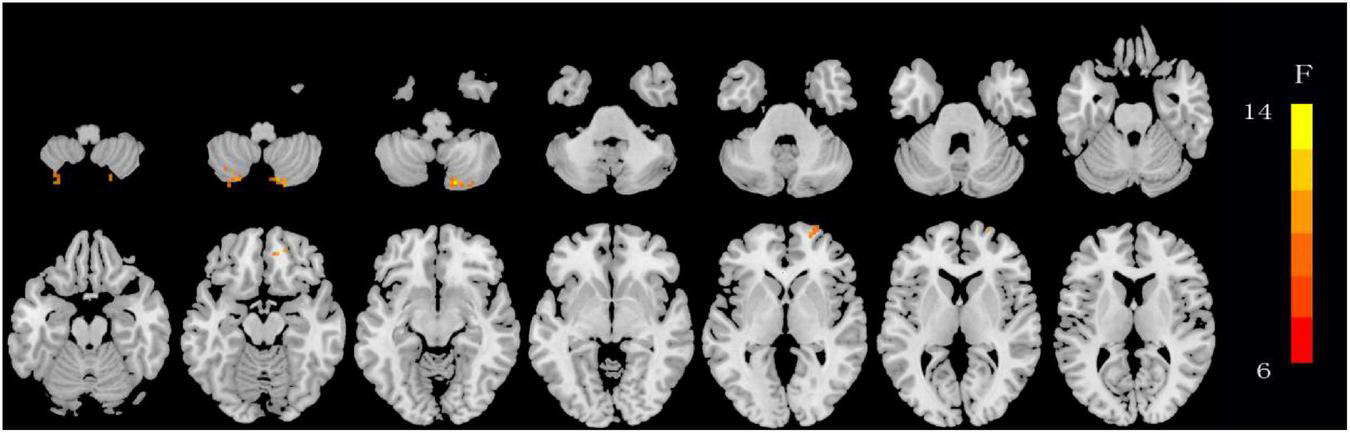

The ANOVA results revealed that the OSA-nMCIs, OSA-MCIs, and HCs groups exhibited significant dALFF variability in the bilateral cerebellum posterior lobe, right medial frontal gyrus, and bilateral superior frontal gyrus (Figure 1 and Table 2). For the voxel-based zCVALFF maps, one-sample t-tests were to identify the spatial distribution in three groups, respectively (Figure 2). Compared with OSA-nMCI patients, OSA-MCI patients exhibit decreased dALFF variability in the bilateral cerebellum posterior lobe and left superior frontal gyrus (Figure 3 and Table 2). Compared with HCs, OSA-nMCI patients had increased dALFF variability in the right cerebellar posterior lobe (Figure 4 and Table 2). However, there were no statistically significant differences in dALFF variability between the OSA-MCI and HC groups.

FIGURE 2

Maps showing differences in dynamic amplitude of low-frequency fluctuation (dALFF) in OSA without MCI (OSA-nMCI), OSA with MCI (OSA-MCI), and healthy control (HC) groups. The hot color indicates significantly differences dALFF brain area. Differences between the groups were calculated using analysis of variance (ANOVA) with the threshold set at voxel P < 0.05 and cluster P < 0.005 with GRF correction.